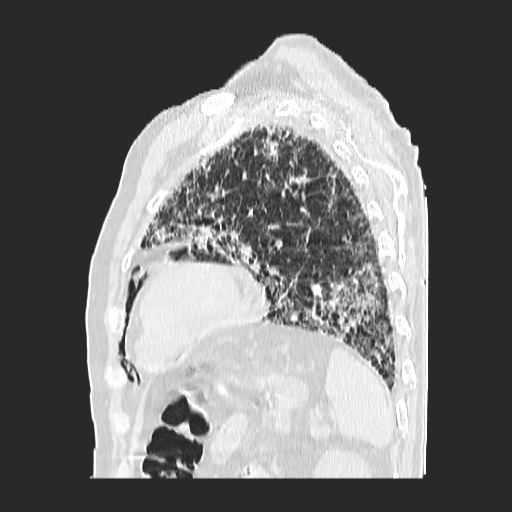

El parénquima pulmonar izquierdo muestra un infiltrado intersticial difuso que causa engrosamiento del septum axial, además del fenómeno de bronquiectasias quísticas se observan pequeñas bulas enfisematosas de localización subpleural que compromete ambas bases pulmonares.

Se observan imágenes de vidrio despulido en todo el lóbulo inferior izquierdo, el cual compromete los segmentos de la língula del segmento superior y medio

El parénquima pulmonar derecho muestra infiltrado intersticial en imagen de vidrio despulido con evidencia de lesiones subpleurales que representan bullas enfisematosas de diferentes tamaños.

Al utilizar un contraste Minip, se observan bronquiectasias cilíndricas en el extremo del lóbulo superior derecho, observándose un patrón de panal de abeja situada en la región apical del lóbulo superior izquierdo.

Bronquiectasias cilíndricas, bullas enfisematosas basales bilaterales